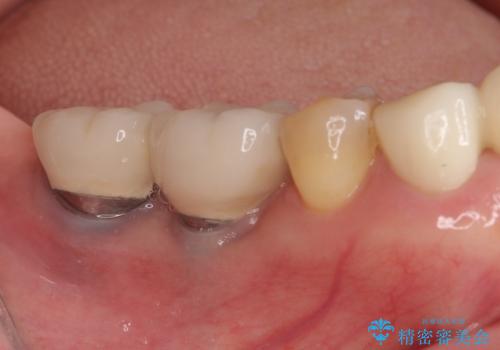

[歯周病治療] 歯周補綴 インプラント補綴

![[歯周病治療] 歯周補綴 インプラント補綴の症例 治療前](https://seimitsushinbi.jp/wp/wp-content/uploads/2020/03/067ed603e15bc4c623e950ffbd6c0829-500x350.jpg?v=1585493851)